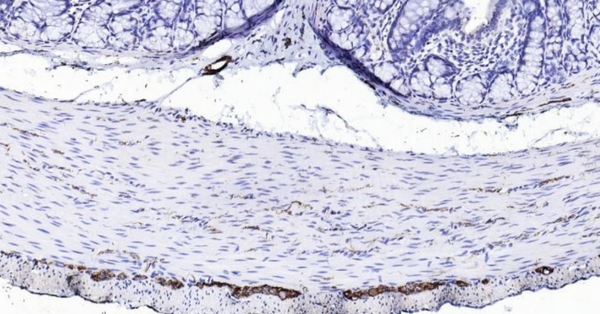

Immunohistochemical analysis of paraffin embedded rat colon tissue slide using IHC0108R (Rat Peripherin IHC Kit).

Peripherin is a 57kD type III intermediate filament that is a specific marker for peripheral neurons, including enteric ganglion cells. Peripherin is expressed in the developing peripheral nervous system and is highly enriched in neuronal derivatives of the neural crest. Peripherin offers an advantage over other neural markers, such as S100 and NSE in that it does not stain chrmaffin cell types.